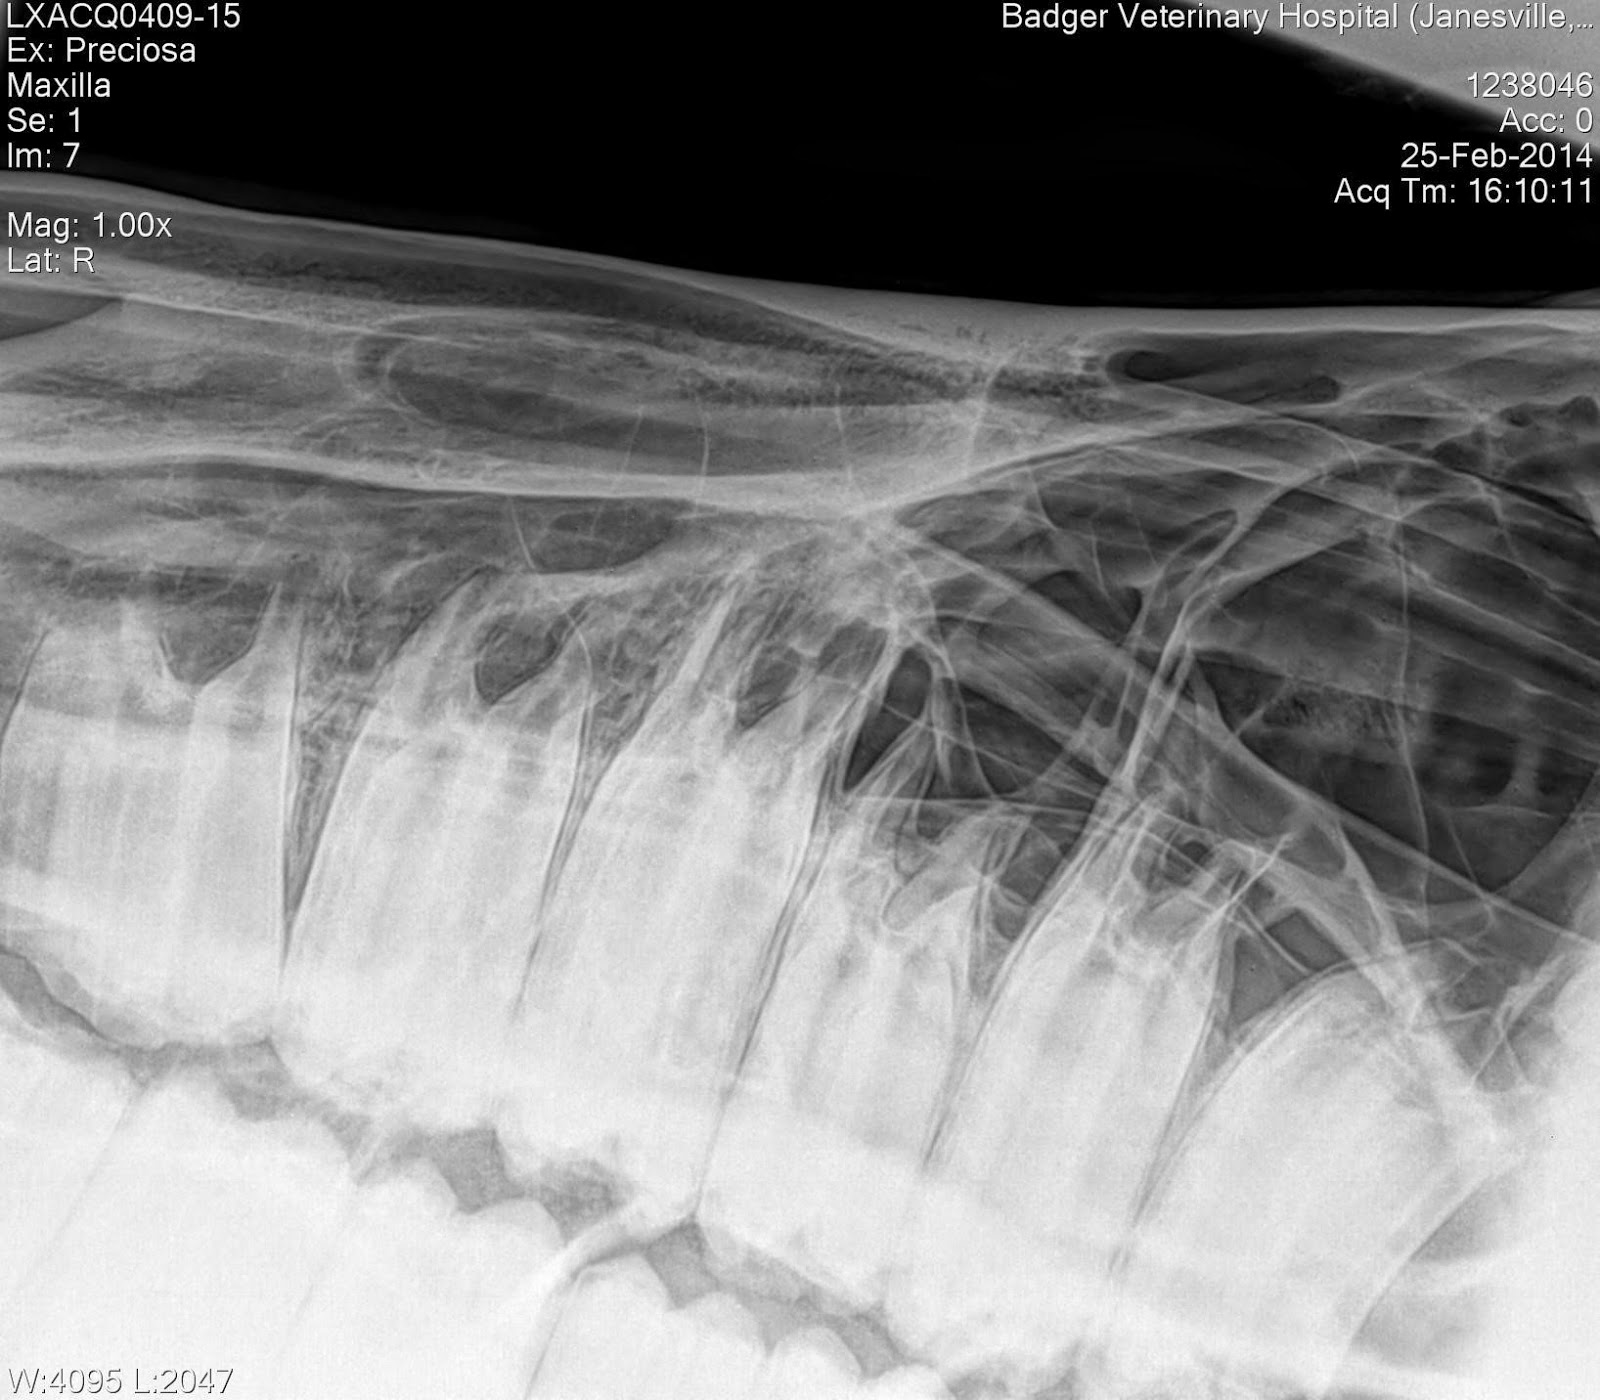

Toria Waldron DVM, Badger Veterinary Hospital Equine Dentistry Not Equine Dental Radiograph Technique Diagnostic radiographic imaging of the equine skull and dentition requires careful positioning and technique. Obtaining radiographs of the horse’s skull. The excellent contrast between air, bone,. This article, the third in a series of four to review. A diagnostic equine dental radiographic study. Equine skull radiography to be a valuable tool in the diagnosis and management of sinus and dental. Equine Dental Radiograph Technique.